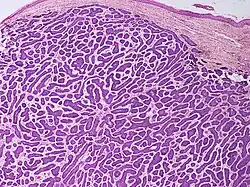

Nodular basal-cell carcinoma

Nodular basal-cell carcinoma (also known as "classic basal-cell carcinoma") accounts for 50% of all BCC.[29] It most commonly occurs on the sun-exposed areas of the head and neck.[30]: 748 [31]: 646 Histopathology shows aggregates of basaloid cells with well-defined borders, showing a peripheral palisading of cells and one or more typical clefts.[29] Such clefts are caused by shrinkage of mucin during tissue fixation and staining.[32] Central necrosis with eosinophilic, granular features may also be present, as well as mucin. The heavy aggregates of mucin determine a cystic structure. Calcification may also be present, especially in long-standing lesions.[29] Mitotic activity is usually not so evident, but a high mitotic rate may be present in more aggressive lesions.[29] Adenoidal BCC can be classified as a variant of NBCC, characterized by basaloid cells with a reticulated configuration extending into the dermis.[29]